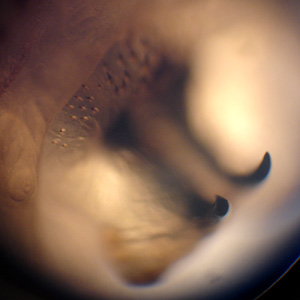

A 75-year-old man developed a lesion on his right forearm. The lesion developed approximately one month after returning from a trip to Costa Rica. The patient’s attending physician removed what appeared to be a fly larva. The larva was sent to the hospital’s Microbiology Department for further identification. Figure A and B show the ventral and lateral sides of the larva, respectively. Figure C shows a close-up of the mouthparts. Figure D shows a close-up of the cuticular spines. What is your identification? Based on what criteria?

Figure C